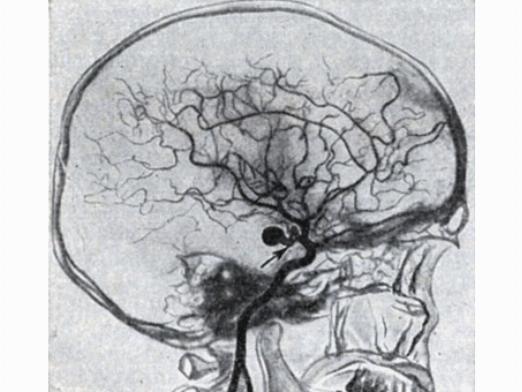

Снимки и иллюстрации микроаневризм сосудов головного мозга